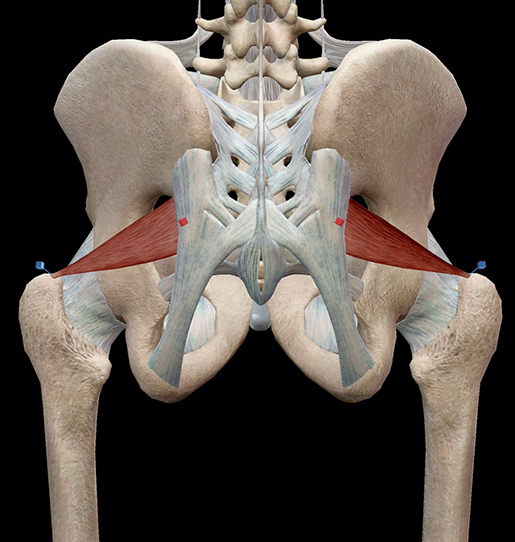

Анатомия мышц: Пириформис